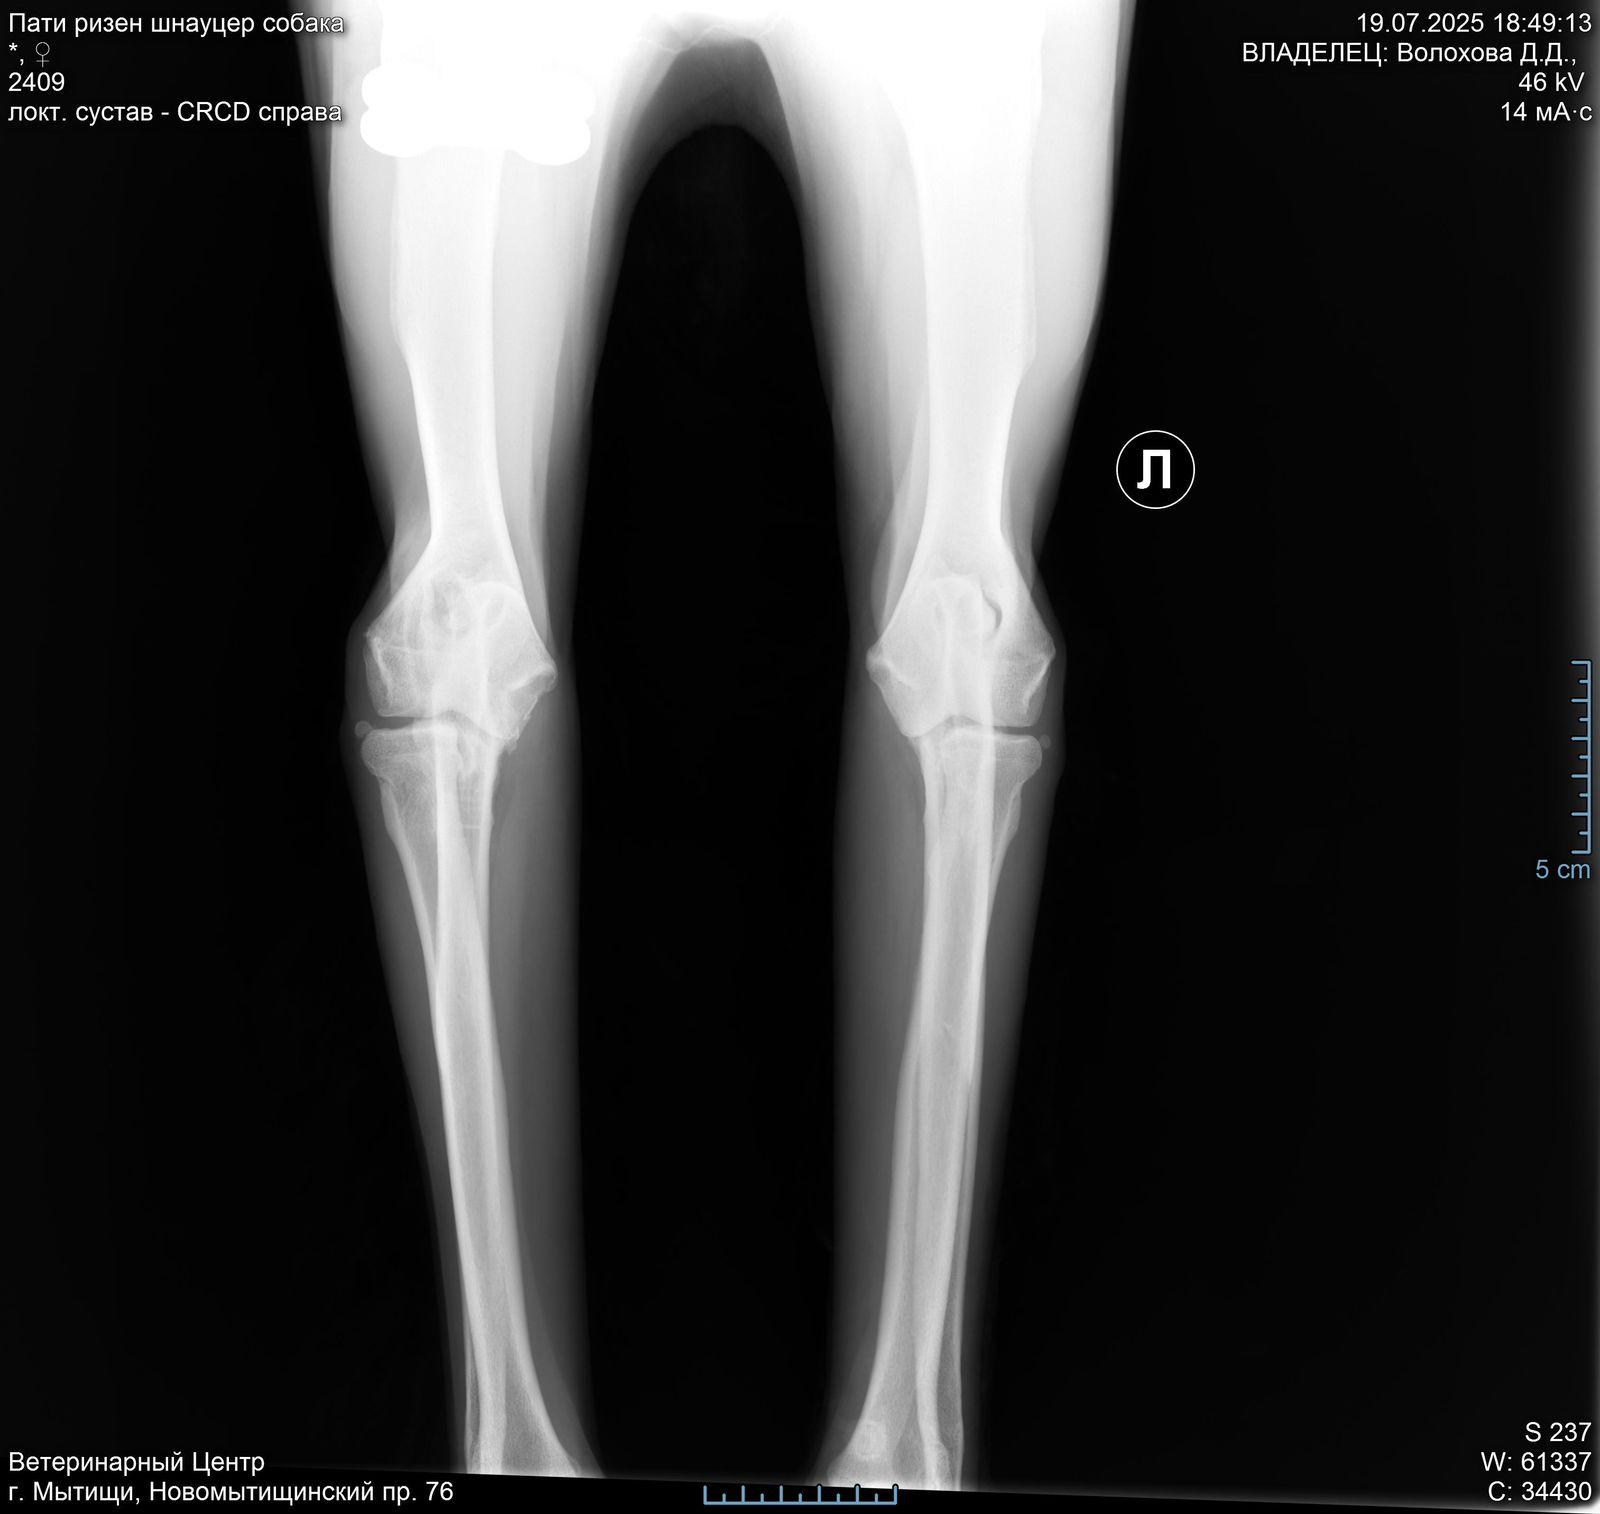

Лапа

В правом локтевом суставе у Пати болтается 2 осколка кости( от мыщелков).

Их надо убирать.

Проблема не приобретенная у нас, а врожденная или травма в прошлой жизни.

Операция сложная, и делается 2 способами: на открытом суставе или через артроскоп ( если осколки меньше 1 см).

Поэтому вначале требуется КТ, чтоб понимать, какой метод в нашем случае актуален.

Есть шансы поиметь осложнения при обоих. У каждого есть плюсы и минусы.

Но пока есть шанс убрать осколки и жить вполне обычной жизнью ( не спортивной, но и не инвалид).

Артроз сустава никуда не исчезнет, но если повезет, и сильно прогрессировать не будет.

При таком поражении сустава удивительно, что нет выраженной хромоты.

Задние ноги не идеал, но портить жизнь не должны.

Левый локтевой пока под вопросом, есть там проблемы или нет. КТ покажет.